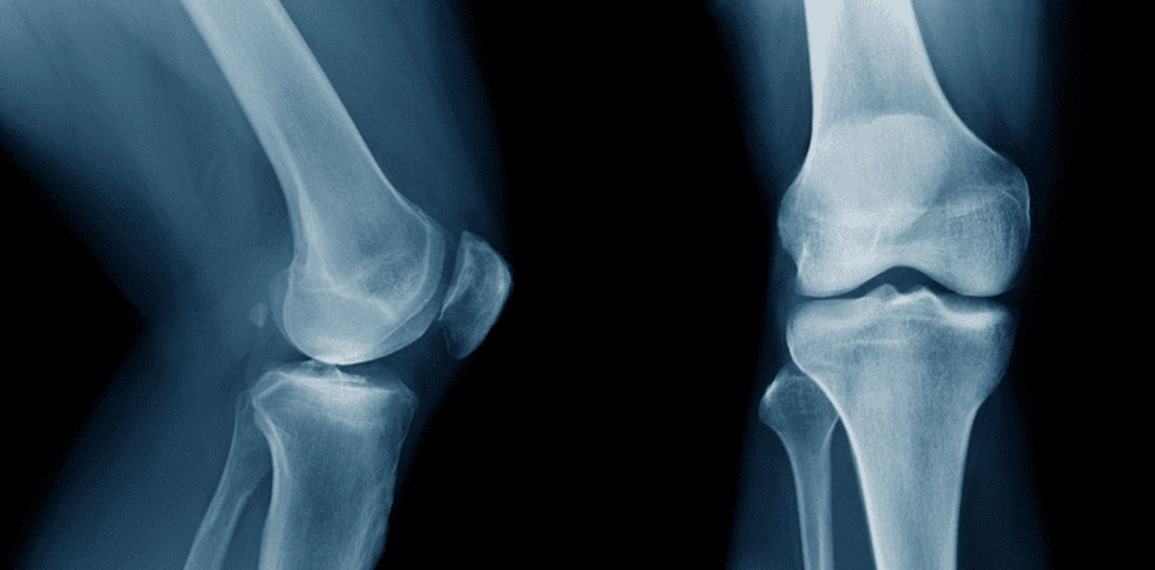

In a significant advancement for orthopaedic medicine, researchers in China have introduced Bone-02, a bio-adhesive that can heal fractures in just three minutes. This innovative material not only bonds bone fragments but also dissolves naturally as the body heals, potentially replacing the need for traditional metal plates and screws. The implications of this development could transform fracture treatment for millions of patients globally.

The creation of Bone-02 comes from a team at Zhejiang University School of Medicine and Xiaoshan Hospital, following almost a decade of research. Lead investigator Professor Pan Xunwu emphasized that traditional methods of fracture repair often lead to complications, including the loss of bone fragments and prolonged recovery times. “In the process, bone fragments were often lost, reducing bone mass and ultimately negatively impacting patients’ quality of life,” he stated during a discussion with Chosun Ilbo.

Inspired by the natural adhesive properties of oysters, Bone-02 mimics their ability to bond even in wet, blood-rich environments. The research team undertook hundreds of formulation changes and extensive animal trials to develop a glue that balances biocompatibility with the necessary adhesive strength. Unlike conventional metal implants, which require surgical removal, Bone-02 is fully biodegradable and absorbed by the body within six months, reducing the need for follow-up surgeries.

Clinical trials involving more than 150 patients have showcased the adhesive’s effectiveness. For instance, a patient with a comminuted wrist fracture had their bone fragments secured in just three minutes through a small incision of 2 to 3 cm. In contrast, traditional treatments would necessitate a larger incision and subsequent removal surgery a year later. Remarkably, the patient regained full wrist function after only three months without complications.

The adhesive demonstrates impressive metrics: it can withstand over 181 kg of tensile strength, has a compressive strength of approximately 10 MPa, and a shear strength near 0.5 MPa. These specifications suggest that Bone-02 could rival or even replace standard steel plates and screws, as highlighted by Global Times.

According to Lin Xianfeng, an associate chief orthopaedic surgeon at Sir Run Run Shaw Hospital and co-lead researcher, Bone-02 could change the landscape of fracture treatment. The adhesive’s rapid bonding capabilities and straightforward application promise to significantly reduce surgery times and lessen intraoperative damage. This advancement addresses long-standing issues in the development of bone adhesives, which have persisted since the 1940s. Previous attempts involving gelatin, epoxy resins, and acrylates failed due to inadequate biocompatibility and strength.

Bone-02 is currently undergoing multi-centre randomised controlled clinical trials, which are the benchmark for regulatory approval in medical research. If these trials yield positive results, the adhesive could be introduced in hospitals worldwide within the next few years. Medical experts remain cautiously optimistic, noting the necessity for peer-reviewed studies and adherence to international safety standards. Nevertheless, early evidence suggests that Bone-02 may provide a faster and safer path to recovery for millions of patients suffering from fractures.